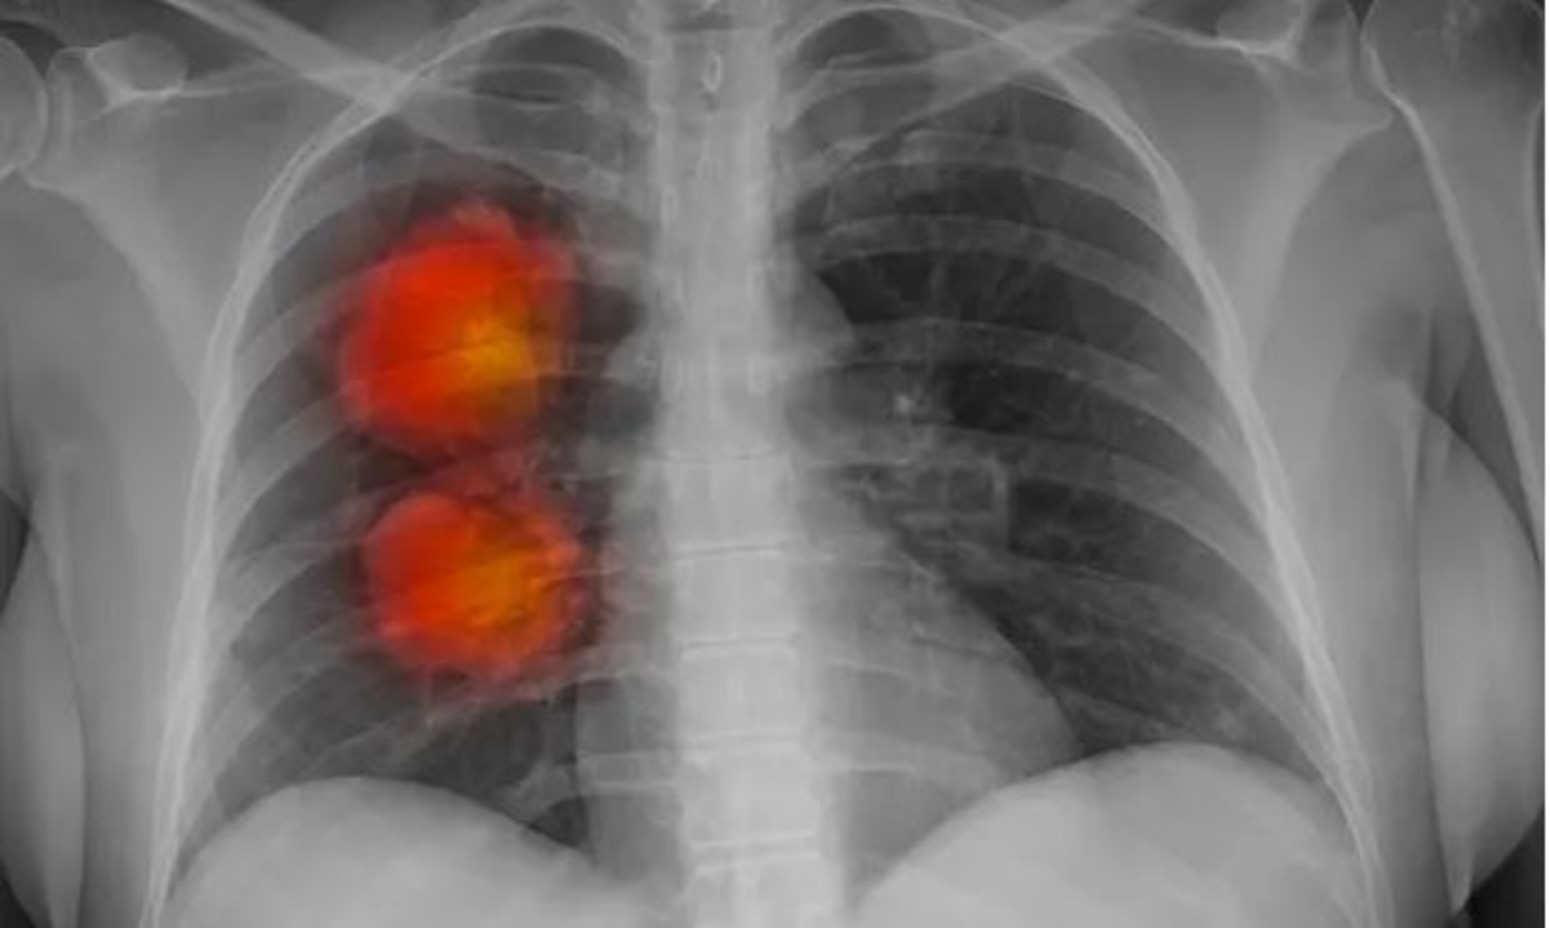

Инструмент искусственного интеллекта был разработан экспертами фонда Royal Marsden NHS, Института исследования рака в Лондоне и Имперского колледжа Лондона. Он может определить, являются ли аномальные новообразования, обнаруженные на КТ, злокачественными.

Команда использовала компьютерную томографию около 500 пациентов с большими узлами в легких для разработки алгоритма искусственного интеллекта. Этот метод может извлекать жизненно важную информацию из медицинских изображений, которые трудно заметить человеческому глазу.

Согласно первоначальным результатам, модель ИИ, по-видимому, точно идентифицирует раковые крупные узелки в легких.